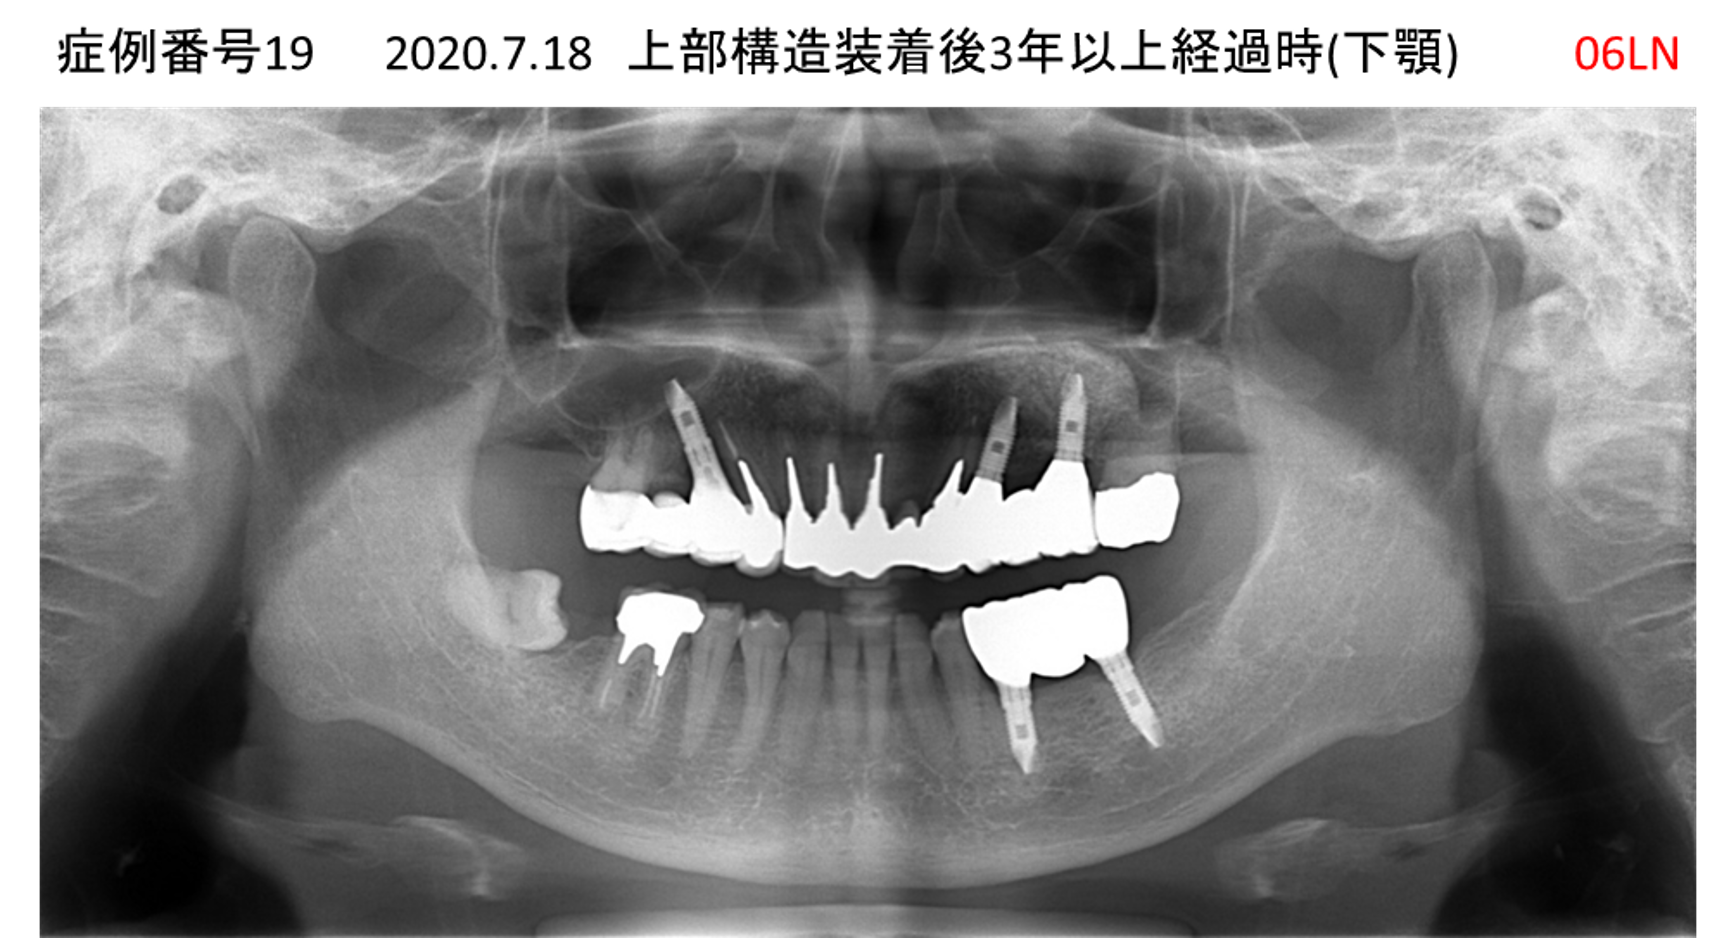

揺れている歯が多くて噛めない患者様のインプラント症例

| 治療名称 |

インプラント |

| 治療費用 |

440万円+税 |

| 治療期間 |

8か月 |

| 患者さんの症状(主訴) |

上の歯をはじめ、揺れている歯が多くて噛めない。食事ができない。 |

| 治療内容 |

サイナスリフト 抜歯即時インプラント |

| 治療結果 |

食事に困らない。見た目がとても良くなった。 |

| 治療の注意点(リスク/副作用) |

インプラントが壊れたら再治療が必要 |